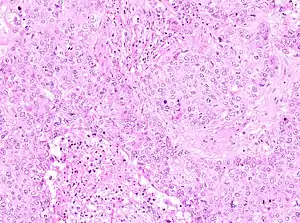

The microscopic histopathology of PACB tumors prepared with hematoxylin and eosin staining shows that >90% of the tumors consist of apocrine gland-like tissue. The lesions must also show that tumor cells have broken through their ducts of origin to invade adjacent tissue in at least one area. Most of the tumor cells (termed type A cells[15]) typically appear somewhat more irregular than normal apocrine gland cells. They have abundant eosinophilic (i.e. pink due to the uptake of the eosin dye) cytoplasm which contain numerous granules[11] and large mitochondria.[15] Their nuclei are large, variably sized and shaped, have multiple nucleoli (which are eosinophilic[11] and may be distinctively large in size[14]), and are surrounded by highly visible nuclear membranes. The cells are arranged into solid sheets, nests, papillae, and/or cords (see Figs. 1 and 2).[11] The tumor cells' cytoplasmic granules test positive when treated with the PAS diastase stain.[16] Binucleated cells, i.e. cells with two nuclei, are common.[10] Less commonly, type B apocrine cells are present; these cells have a more foamy and vacuolated cytoplasm (i.e. containing multiple vacuoles) than type A cells[15] and often resemble foamy histiocytes or sebaceous gland cells.[17] The tumor cells have low to moderate rates of proliferation based on their Ki-67 protein levels.[7] PACB tissues may have localized areas that contain mucin-like secretions within their luminal ducts,[10] localized areas of necrosis (i.e. foci containing dead or dying cells), and/or microcalcifications spotted throughout the apocrine tissue.[11] The stroma (i.e. connective tissue between the sheets, nests, papilla and cords of cells) typically contains non-malignant, infiltrating lymphocytes (see Fig. 3). In an examination of 41 PABC tumors, 33 (80.5%) had <50% of their stroma tissues infiltrated with these cells while 8 (19.5%) had ≥50% of their stroma tissues infiltrated with them. Tumors with ≥50% of their stroma infiltrated with lymphocytes tended to have carcinoma cells that had high rates of proliferation.[11] Metastatic and recurrent PACB tumors have a histopathology similar to their original primary tumors.[14]

Non-invasive apocrine carcinoma of the breast, i.e. apocrine carcinoma in situ, is classified as a variant of the ductal carcinoma in situ tumors of the breast; it is therefore termed apocrine ductal carcinoma in situ (ADCIS).[9] ADCIS tumors have appreciable areas with apocrine tissue-like histopathology, i.e. areas composed of apocrine cells that have, to varying extents, the abnormal cytoplasmic, nuclear, and nucleolar features found in PACB (see Fig 4). Unlike PACB, the apocrine carcinoma cells in ADCIS have by definition not spread beyond their ducts of origin to invade nearby non-ductal tissue and have not metastasized to local lymph nodes or distant tissues.[4] While there is no consensus on the criteria used for its diagnosis, ADCIS is most often defined as a non-invasive breast tumor consisting of lactiferous ducts that are filled with neoplastic apocrine cells;[4] the cells in these tumors, similar to those in PACB, are estrogen receptor-negative, progesterone-receptor negative, and, in at least 10% of these cells, androgen receptor-positive.[9] Some studies have classified ADCIS as low, intermediate, or high nuclear grade based on how closely the nuclei of their tumor's apocrine cells resemble the nuclei of normal breast cells. In general, high nuclear grade tumor cells have more abnormal nuclei and indicate that this tumor is more aggressive than a lower grade tumor. Low- and intermediate-grade ADCIS tumors may be misdiagnosed as non-cancerous lesions (e.g. as atypical apocrine metaplasia or atypical apocrine hyperplasia) because of their more benign microscopic appearance.[4] ADCIS tumors often have architectural patterns consisting of cribriform (riddled with small holes), micropapillary (thin finger-like growths) and/or solid growth (i.e. do not contain cysts or liquid areas),[4] sites with necrosis, and/or sites with microcalcifications; while these microscopic findings are more common in high nuclear grade ADCIS, their presence supports the diagnosis of ADCIS in low and intermediate tumors.[9] Some authors have proposed that in situ ductal tumors with apocrine histopathology should be larger than 0.2 centimeters in order to be diagnosed as ADCIS.[4][9]